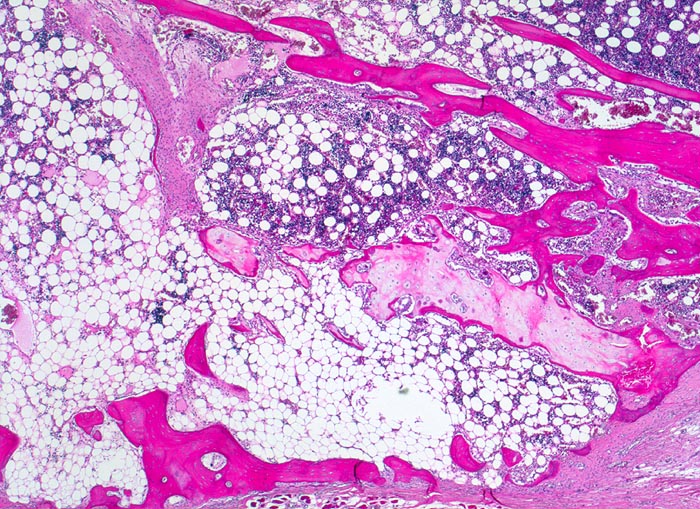

• Alte Rippenfraktur mit dislozierten Frakturenden. Sekundäre Frakturheilung mit Ausbildung eines fibroossären Frakturkallus.

• Extrem dünne Corticalis.

• Spongiosa ausserhalb der Fraktur mit ausgeprägter Osteopenie.

• Die Spongiosabälkchen sind stark verdünnt. Die Osteozyten innerhalb der Spongiosabälkchen sind eng zusammengerückt und die einzelnen Knochenlamellen sind ebenfalls verdünnt.

• Alterskorreliert normozelluläres Knochenmark.